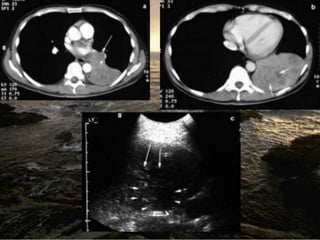

5.1. Pulmonary lesions

The normal aerated lung is difficult to image

because the dramatic change in acoustic impe‐

dance between chest wall and lung results in

specular reflection of ultrasound waves at the

pleura. However, consolidated lung has a tissue

density and echo-texture similar to liver,

analogous to pathological hepatisation. This

removes the change in acoustic impedance at the

pleural interface, and ultrasound waves pass

directly into the affected lung

When patient with lobar or segmental

pneumonia and the lesion is adjacent to pleura

or in the pleural effusion, the pneumonia may be

detected by chest US. A marked consolidation

with air-bronchogram and treelike ramifications

is easily seen Within the consolidated area,

hyperechoic (white) foci may be visible, again

representing a change in acoustic impedance,

but this time at the tissue interface between solid

lung and air-filled bronchi. Subpleural nodule

also can be seen in chest US